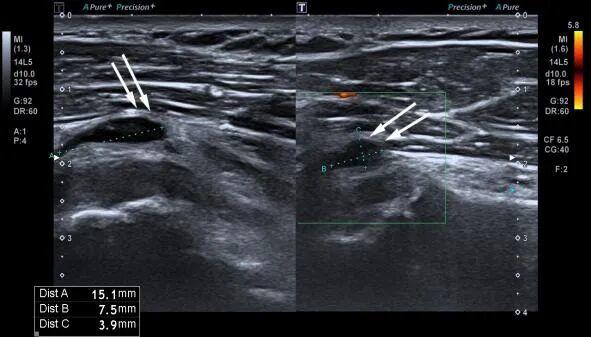

超声显示肌腱部分撕裂(白箭头所示)

当超声探头在您的皮肤上滑动时,它会发射出安全的超声波。这些声波在遇到体内不同的组织(如肌肉、肌腱、韧带、滑囊、神经)时,会产生不同程度的反射。探头再接收这些“回声”,经过计算机的实时处理,立刻在屏幕上形成一幅幅动态清晰的黑白或彩色图像。